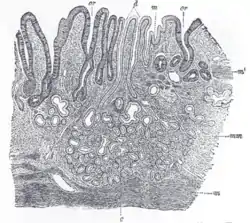

![]() مقطع تشريحي ماخوذ من منطقة البواب في المعدة، تظهر فيها الطبقة المخاطية. | |

صورة تظهر بنية الغشاء المخاطي داخل المعدة .